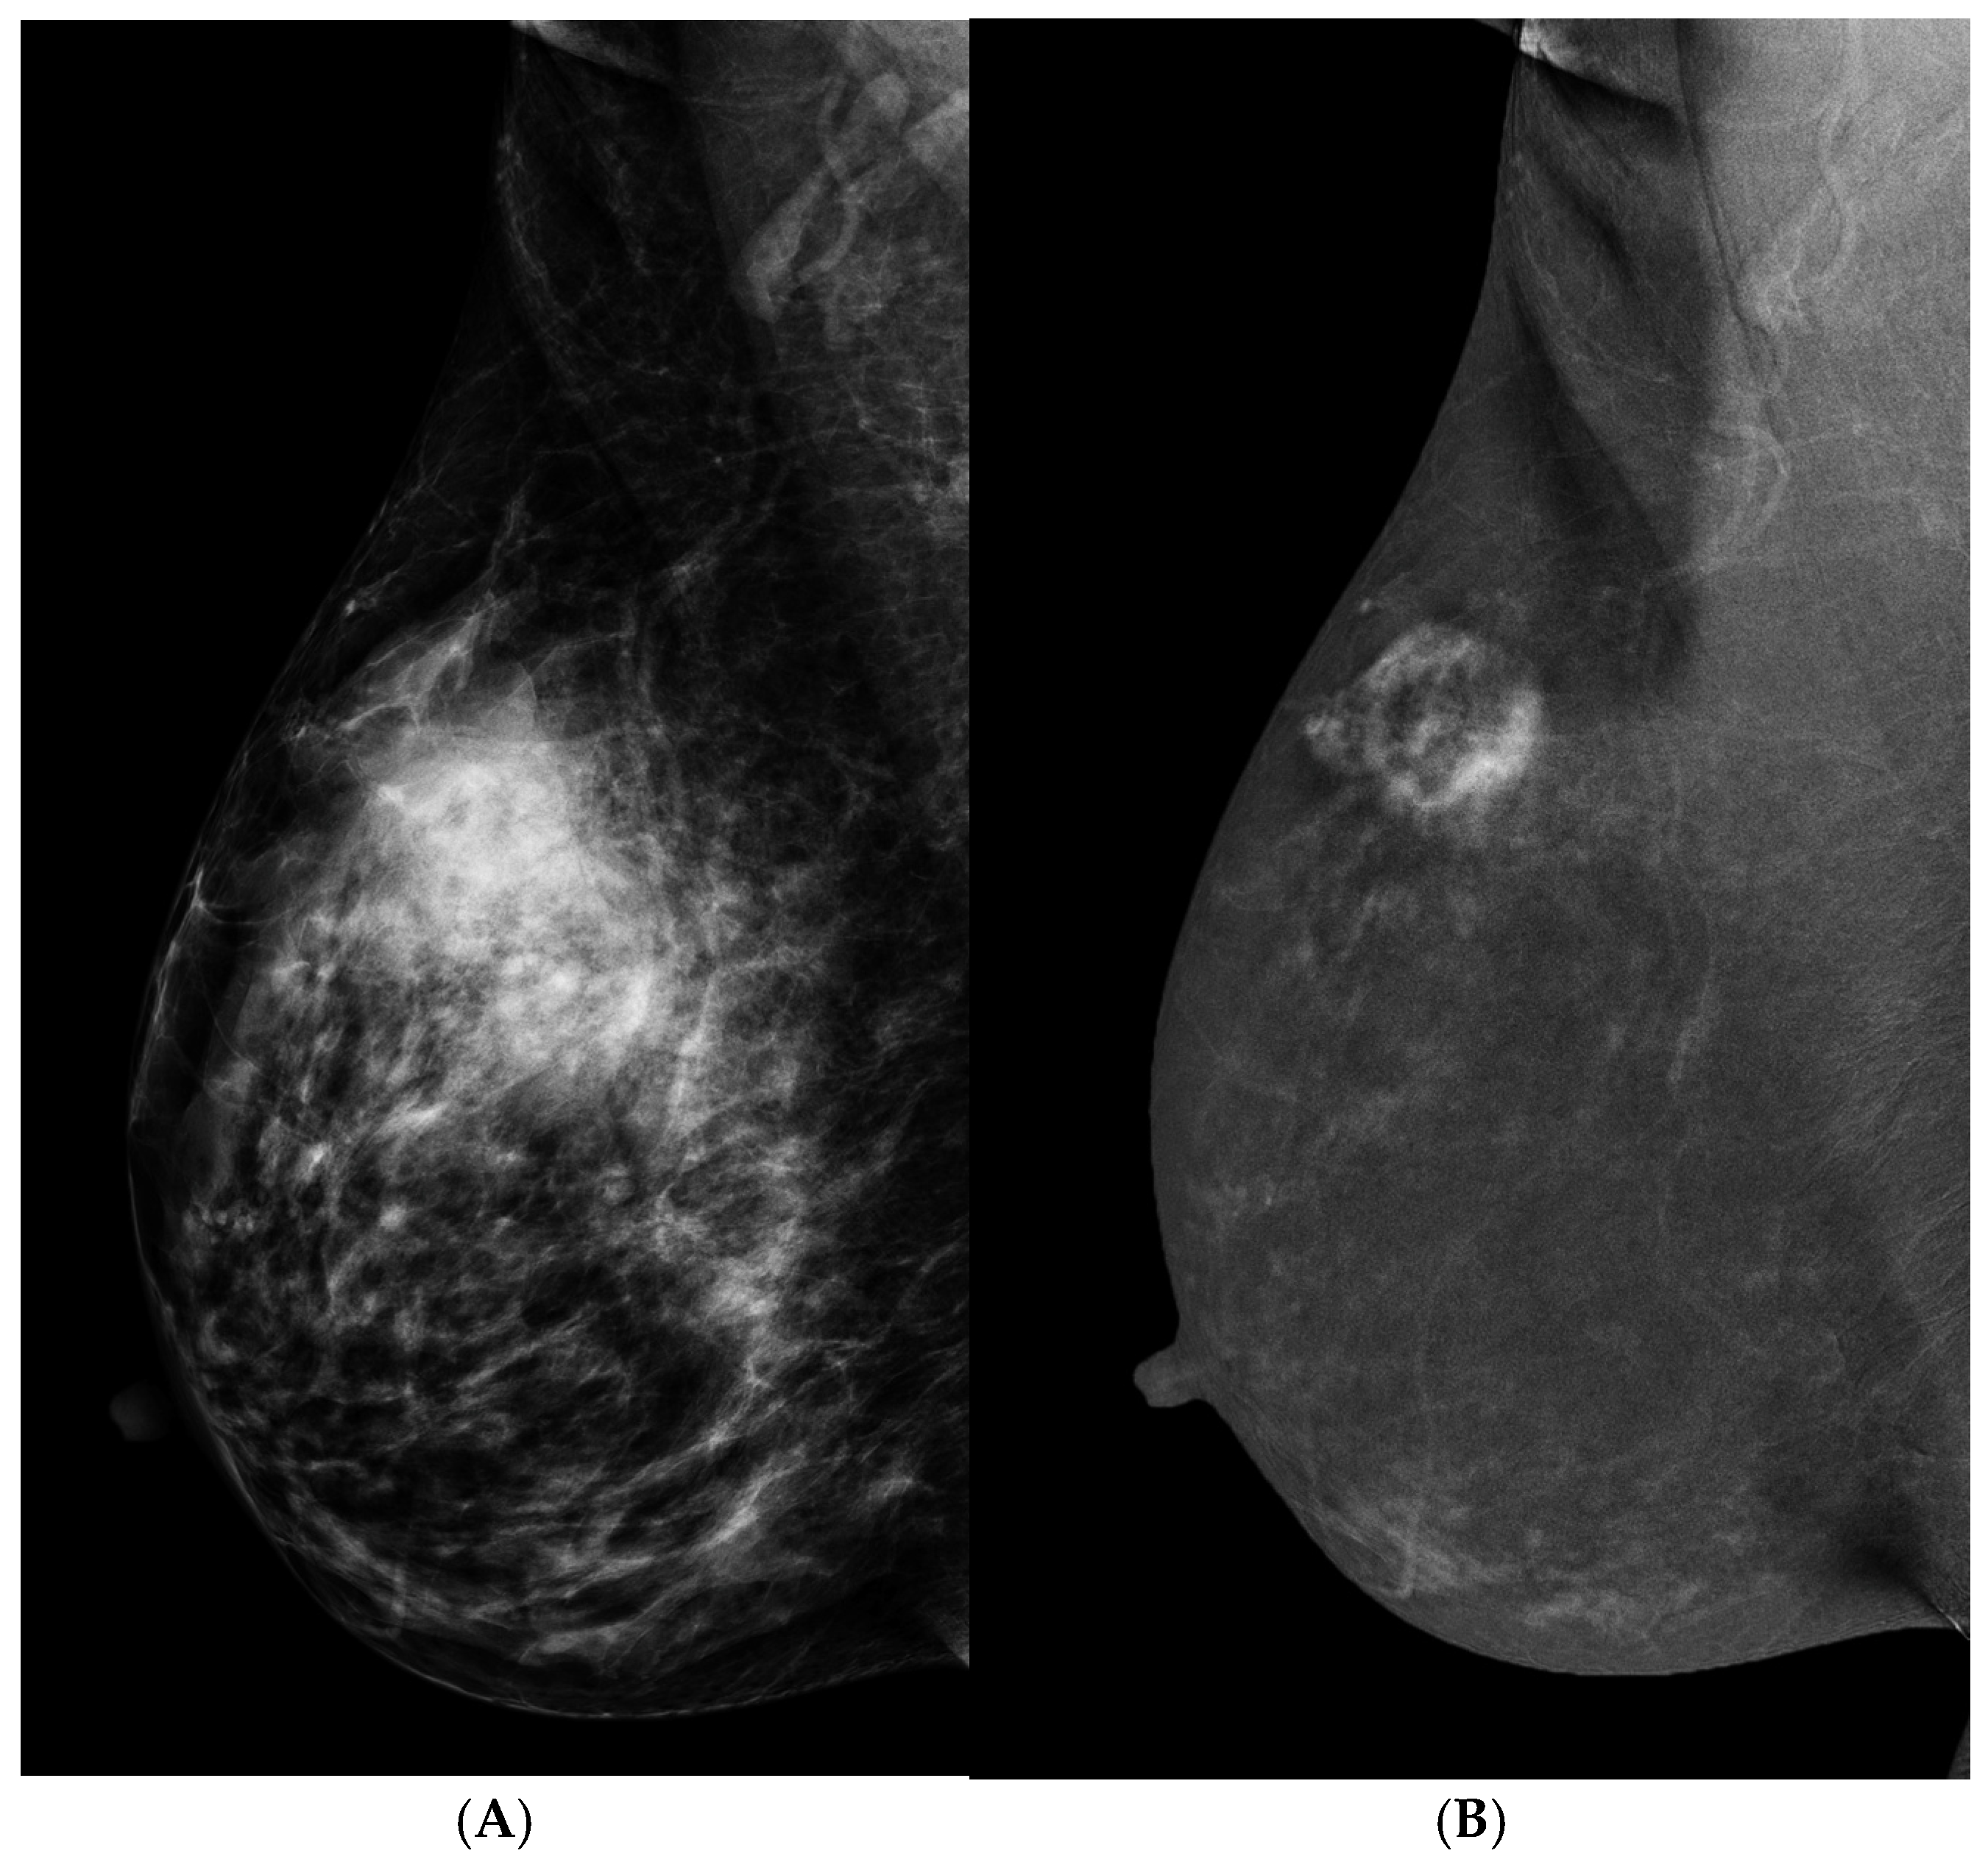

- Schmitz, A.M.; Loo, C.E.; Wesseling, J.; Pijnappel, R.M.; Gilhuijs, K.G. Association between rim enhancement of breast cancer on dynamic contrast-enhanced MRI and patient outcome: Impact of subtype. Breast Cancer Res. Treat. 2014, 148, 541–551. [Google Scholar] [CrossRef]

- Wen, C.; Wang, S.; Ma, M.; Xu, Z.; Zeng, F.; Zeng, H.; Liao, X.; He, Z.; Xu, W.; Chen, W. Breast masses with rim enhancement on contrast-enhanced mammography: Morphological and enhancement features for diagnosis and differentiation of benign and malignant. Br. J. Radiol. 2024, 97, 1016–1021. [Google Scholar] [CrossRef] [PubMed]